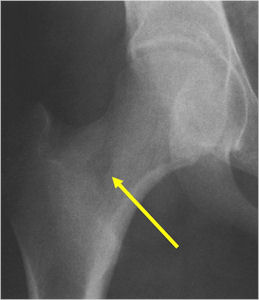

Sites:

- Femoral neck most common but can occur in any bone and any site within a bone (metaphyseal, diaphyseal, epiphyseal; cortical, medullary and periosteal)

- 50% occur in long bones of lower extremities

- Most osteoid osteomas are intracortical in origin but can also occur in the medullary canal or subperiosteal